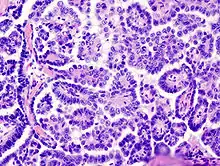

Medium power slide of ovarian serous adenocarcinoma stained using haematoxylin and eosin | |

Papillary serous cystadenocarcinomas may exhibit psammoma bodies upon histopathology.[3]